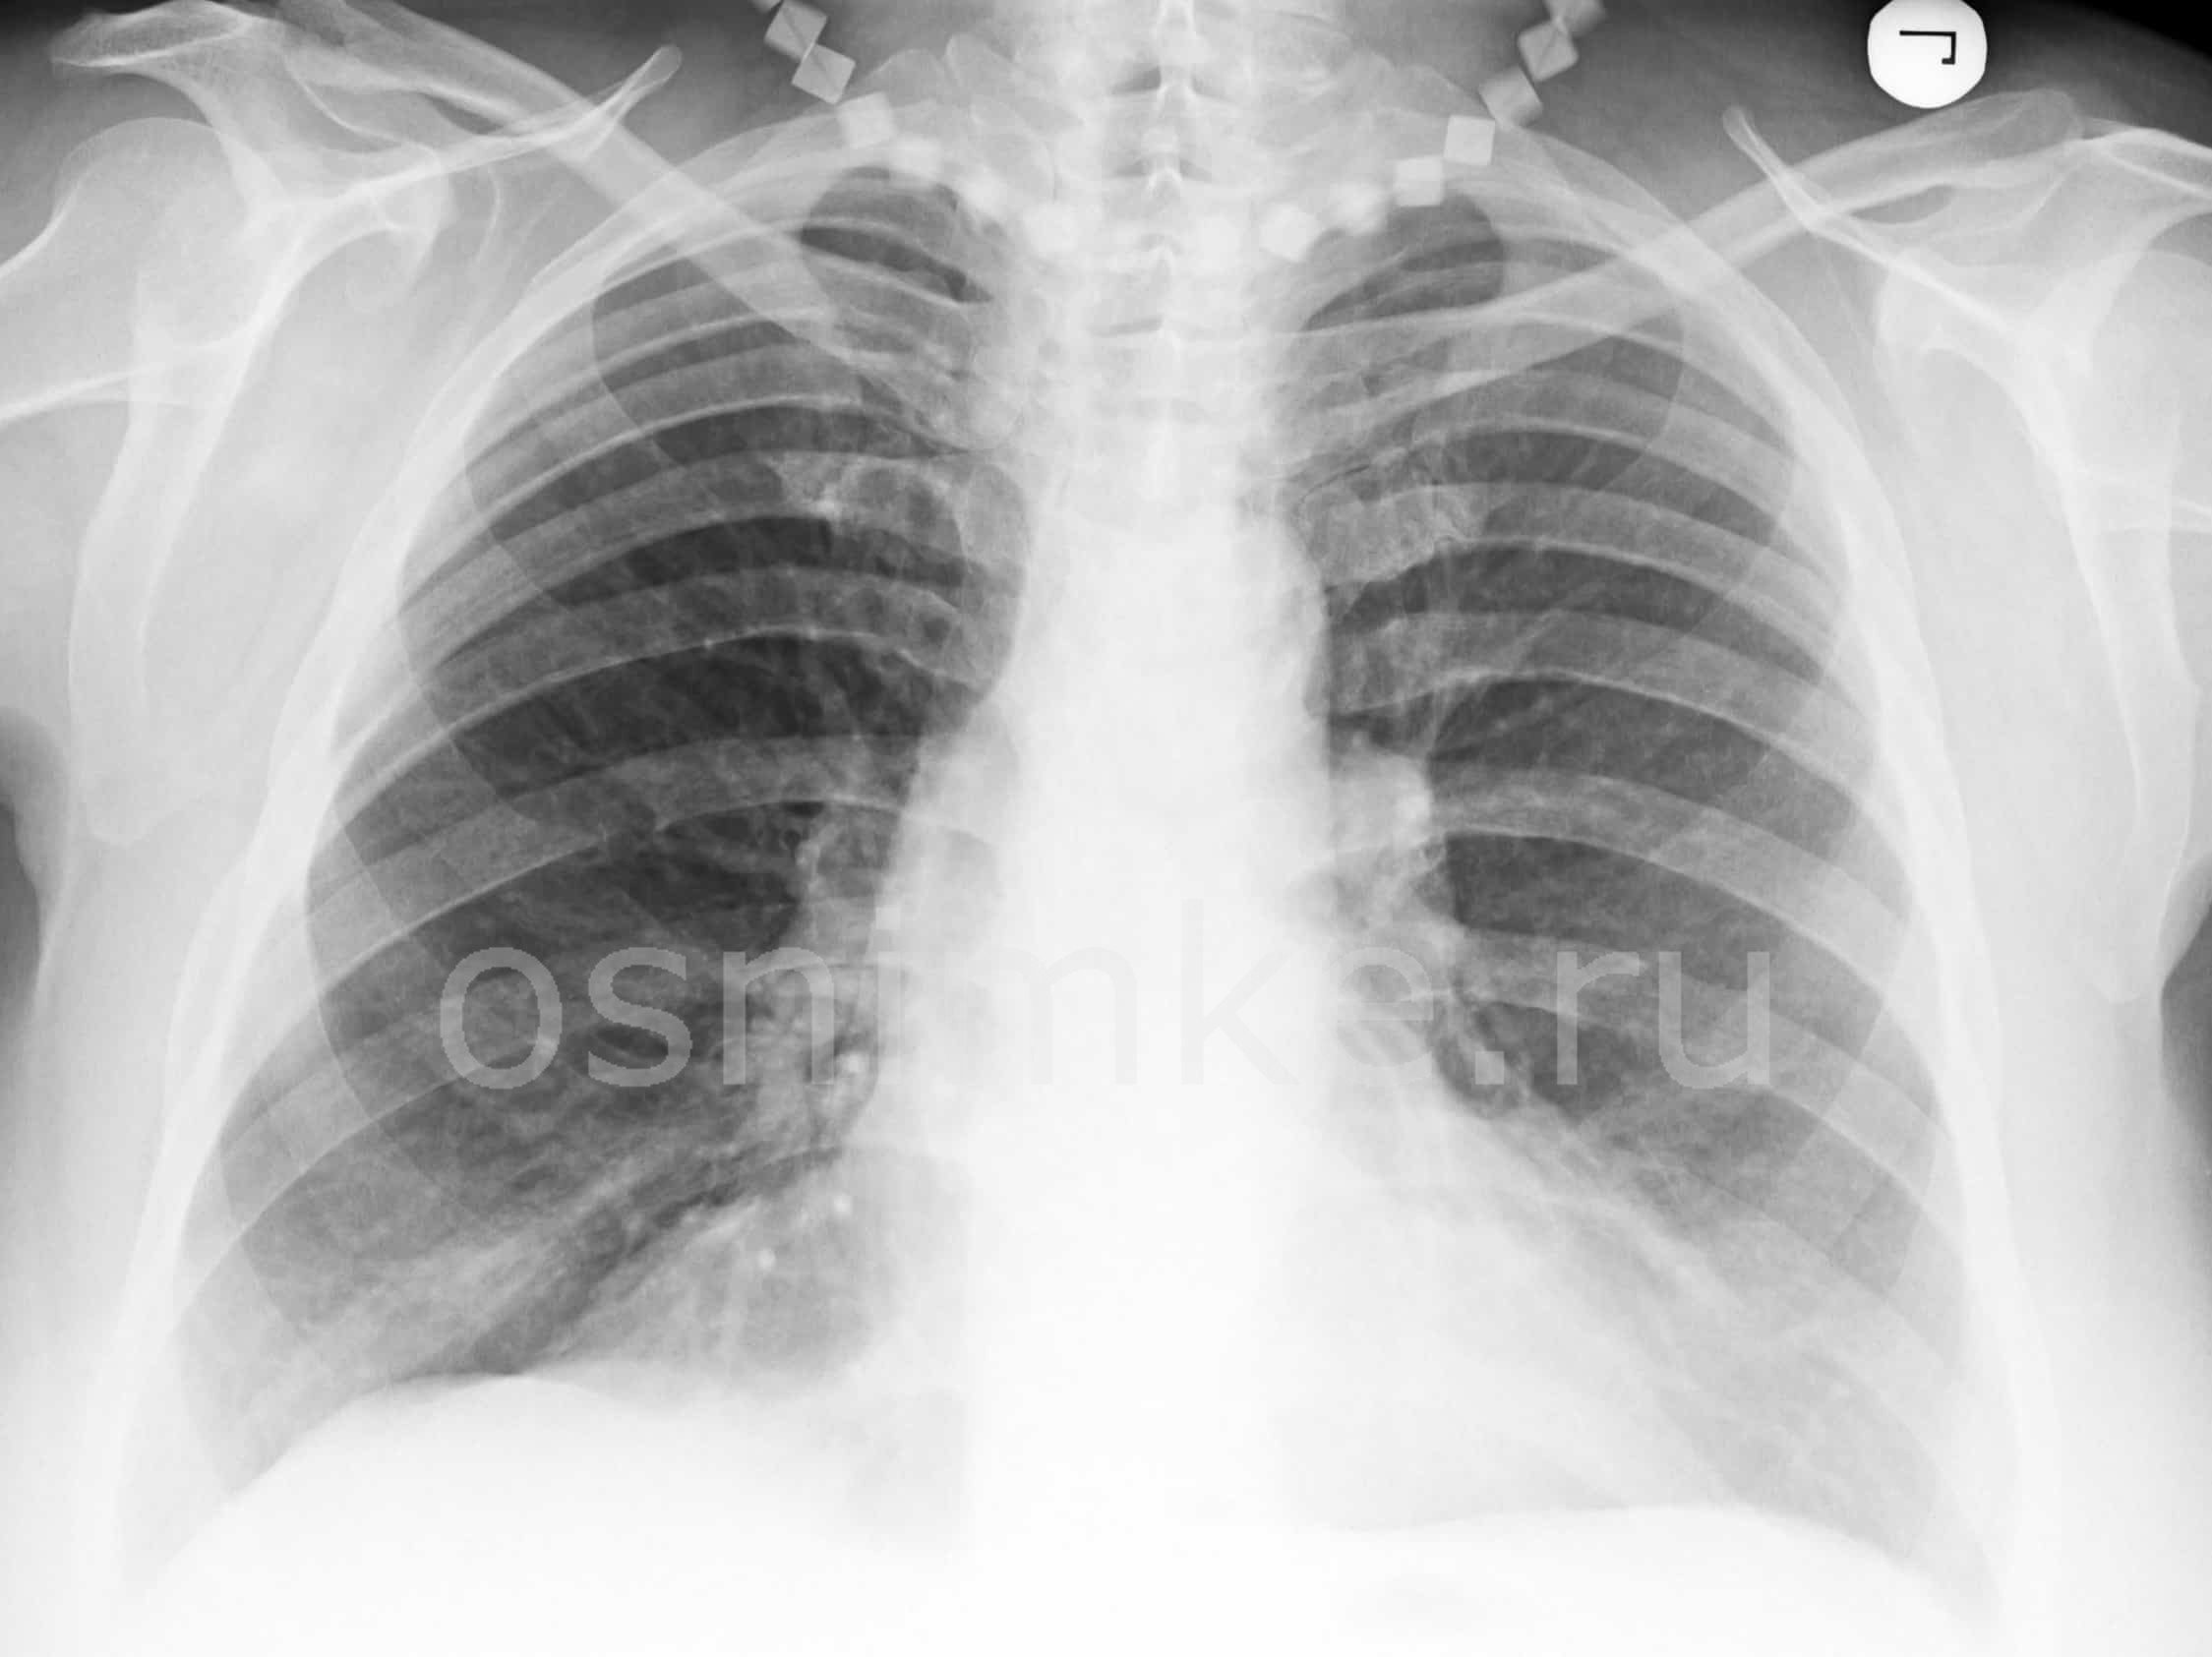

Коронавирусная инфекция прежде всего поражает лёгкие, начиная с горла и переходя по дыхательным путям к жизненно важному органу. Узнаем, как выглядят лёгкие при коронавирусе на рентгене и в чем отличия COVID-19 от пневмонии.

Как коронавирус выглядит на рентгене?

COVID-19 поражает лёгкие. В плевральной полости вокруг органа дыхания накапливается жидкость и он увеличивается в размерах. Лёгочная ткань покрывается рубцами, и из-за этого человеку становится трудно дышать, так как часть органа разрушается и кислороду трудно попасть в кровь.

При рентгеновском излучении лёгких, поражённых коронавирусной инфекцией, наблюдаются затемнения в нижней части органа (на снимке обозначаются белыми пятнами). Пятна называются симптомом “матового стекла”. На рентгене видны пятна, которые обуславливаются наличием жидкости в лёгких.

Симптом “матового стекла” в легких

Симптом “матового стекла” проявляется у больных на фоне поражения лёгких вирусом. Так как дыхательный орган подвергается серьёзным изменениям, в нём появляются зоны повреждений.

Снижается плотность лёгочной ткани. В поражённом участке проявляется умеренно-сниженная воздушность, главным признаком выступает видимость сосудов лёгких и стенок бронхов.

Заметить данный симптом на рентгене сложно, поэтому требуется дополнительно сделать компьютерную томографию.

Типичные признаки проявления симптома “матового стекла”:

- стенки и структура бронхов чётко проглядываются;

- видны затемнения;

- сохраняется сосудистый рисунок;

- повышается прозрачность лёгочной ткани.

Ниже представлены фото, как выглядит симптом “матового стекла” на рентгене и компьютерной томографии:

Как проявляется поражение легких при коронавирусе?

Типичные проявления нарушений органа дыхания при коронавирусной инфекции:

- в лёгких накапливается жидкость и постепенно занимает всё большую площадь;

- поражаются стенки сосудов и клеток крови в лёгких;

- видны затемнения по типу “матового стекла” различного размера, сопровождающееся уплотнением перегородок между альвеолами – пузырями, где капилляры органа обогащаются кислородом;

- в лёгких образуется рубцовая ткань, называющаяся “фиброзом”, вследствие чего снижается растяжимость и эластичность ткани.